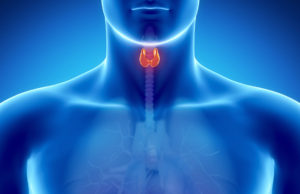

Cum afli daca ai probleme cu tiroida folosind doar un termometru

Cu 50 de ani în urma, doctorul Broda Barnes a aflat ca temperatura corpului nostru poate fi un bun indicator al activitatii glandei tiroide....